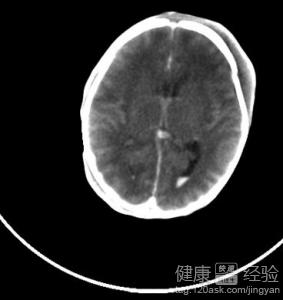

新生兒顱內出血是一種腦部出現損傷的疾病,也是新生兒非常常見的一種非常嚴重的疾病,可能是由於缺氧或者是在生產過程中出現損傷而導致的,最新生兒出現死亡的一個重要原因.硬膜下出血,小腦出血,腦室內出血,蛛網膜下腔出血,腦實質出血都屬於新生兒顱內出血的一種,新生兒出現顱內出血如果存活下來的話也會出現腦積水等神經系統的一些非常嚴重的後遺症.

1新生兒顱內出血的症狀和嬰兒顱內出血的部位和出血的程度都有一定的關系,孩子的中樞神經會出現抑制或者是興奮的症狀,在出後的三天之內就會出現.比如會出現頭圍增加,煩躁,嗜睡,面色蒼白,昏迷等症狀.

2如果剛出生的嬰兒出現顱內出血的話是非常嚴生的,可能會合並肺透明膜病,引起肺部出血,出現呼吸暫停,呼吸節律不齊.特別嚴重的患者可以在生產的過程中就死亡,治愈後也會出現不同程度的後遺症,比如智力低下,癫痫等.

3新生兒在出現顱內出血的時候要盡量不要搬動,保持環境安靜.可以通過維生K來控制住出血,維生素C來改善血管的通透性,同時還要輸入新鮮的全血或者是血漿.可以通過腎上腺皮質激歌詞,甘露醇等來使顱內壓降低.

大部分新生兒顱內出血患者在出生的過程中就會出現死亡,或者是出生之後只會有非常微弱的心跳.通過搶救也可能會出現呼吸困難的現象,但是會出現多種並發症